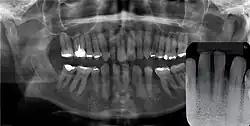

![]() | |

Epstein's pearl shown in the roof of the mouth on a five-week-old infant | |